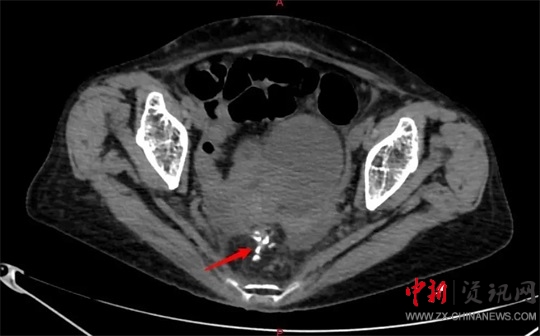

當(dāng)晚9點40分,廖新偉積極協(xié)調(diào),麻醉科手術(shù)部及輸血科密切配合,以劉大勇主刀、副主任醫(yī)師汪麗偉輔助,緊急為侯老太太施行了手術(shù)。打開腹腔,驚人地發(fā)現(xiàn)侯老太太腹腔已被糞便填滿,腸子漲的像氣球那么大。術(shù)中,經(jīng)過沖洗并且減壓腸道后,醫(yī)護團隊在直腸上段發(fā)現(xiàn)一大小約1.5cm破口,一堅硬物嵌頓在破口處,打開腸壁,一排帶鉤的假牙映入眼前。醫(yī)護人員將假牙小心翼翼地完整取出,足足有4cm長。由于侯老太太腹腔污染嚴(yán)重,且腸梗阻時間較長,腸壁水腫十分嚴(yán)重,無法再次重建消化道,于是胃腸外科團隊給老太太做了直腸遠端封閉+乙狀結(jié)腸造口術(shù)?紤]到患者腹腔污染術(shù)后可能出現(xiàn)感染腹腔膿腫等情況,醫(yī)護團隊給侯老太太左右上下總共放了5根引流管。

9月2日凌晨1點半,手術(shù)順利結(jié)束,劉大勇向侯老太家屬展示了取出的假牙,大家才恍然大悟,回想起20多天前老太太說自己的假牙找不到了,一家人尋遍整個屋子都沒有找到,誰也沒想到竟然跑進了肚子里。侯老太太清醒后看到從肚子里取出的假牙,激動地說:“我就納悶?zāi),最近一直尋不到我的假牙,我也沒有印象把它吞到肚子里啊。現(xiàn)在想想它竟然在我肚里20多天,真是后怕啊,幸虧你們市中心醫(yī)院醫(yī)生技術(shù)好,幫我解決大問題啦!”目前,老太太病情平穩(wěn),正在積極康復(fù)中。